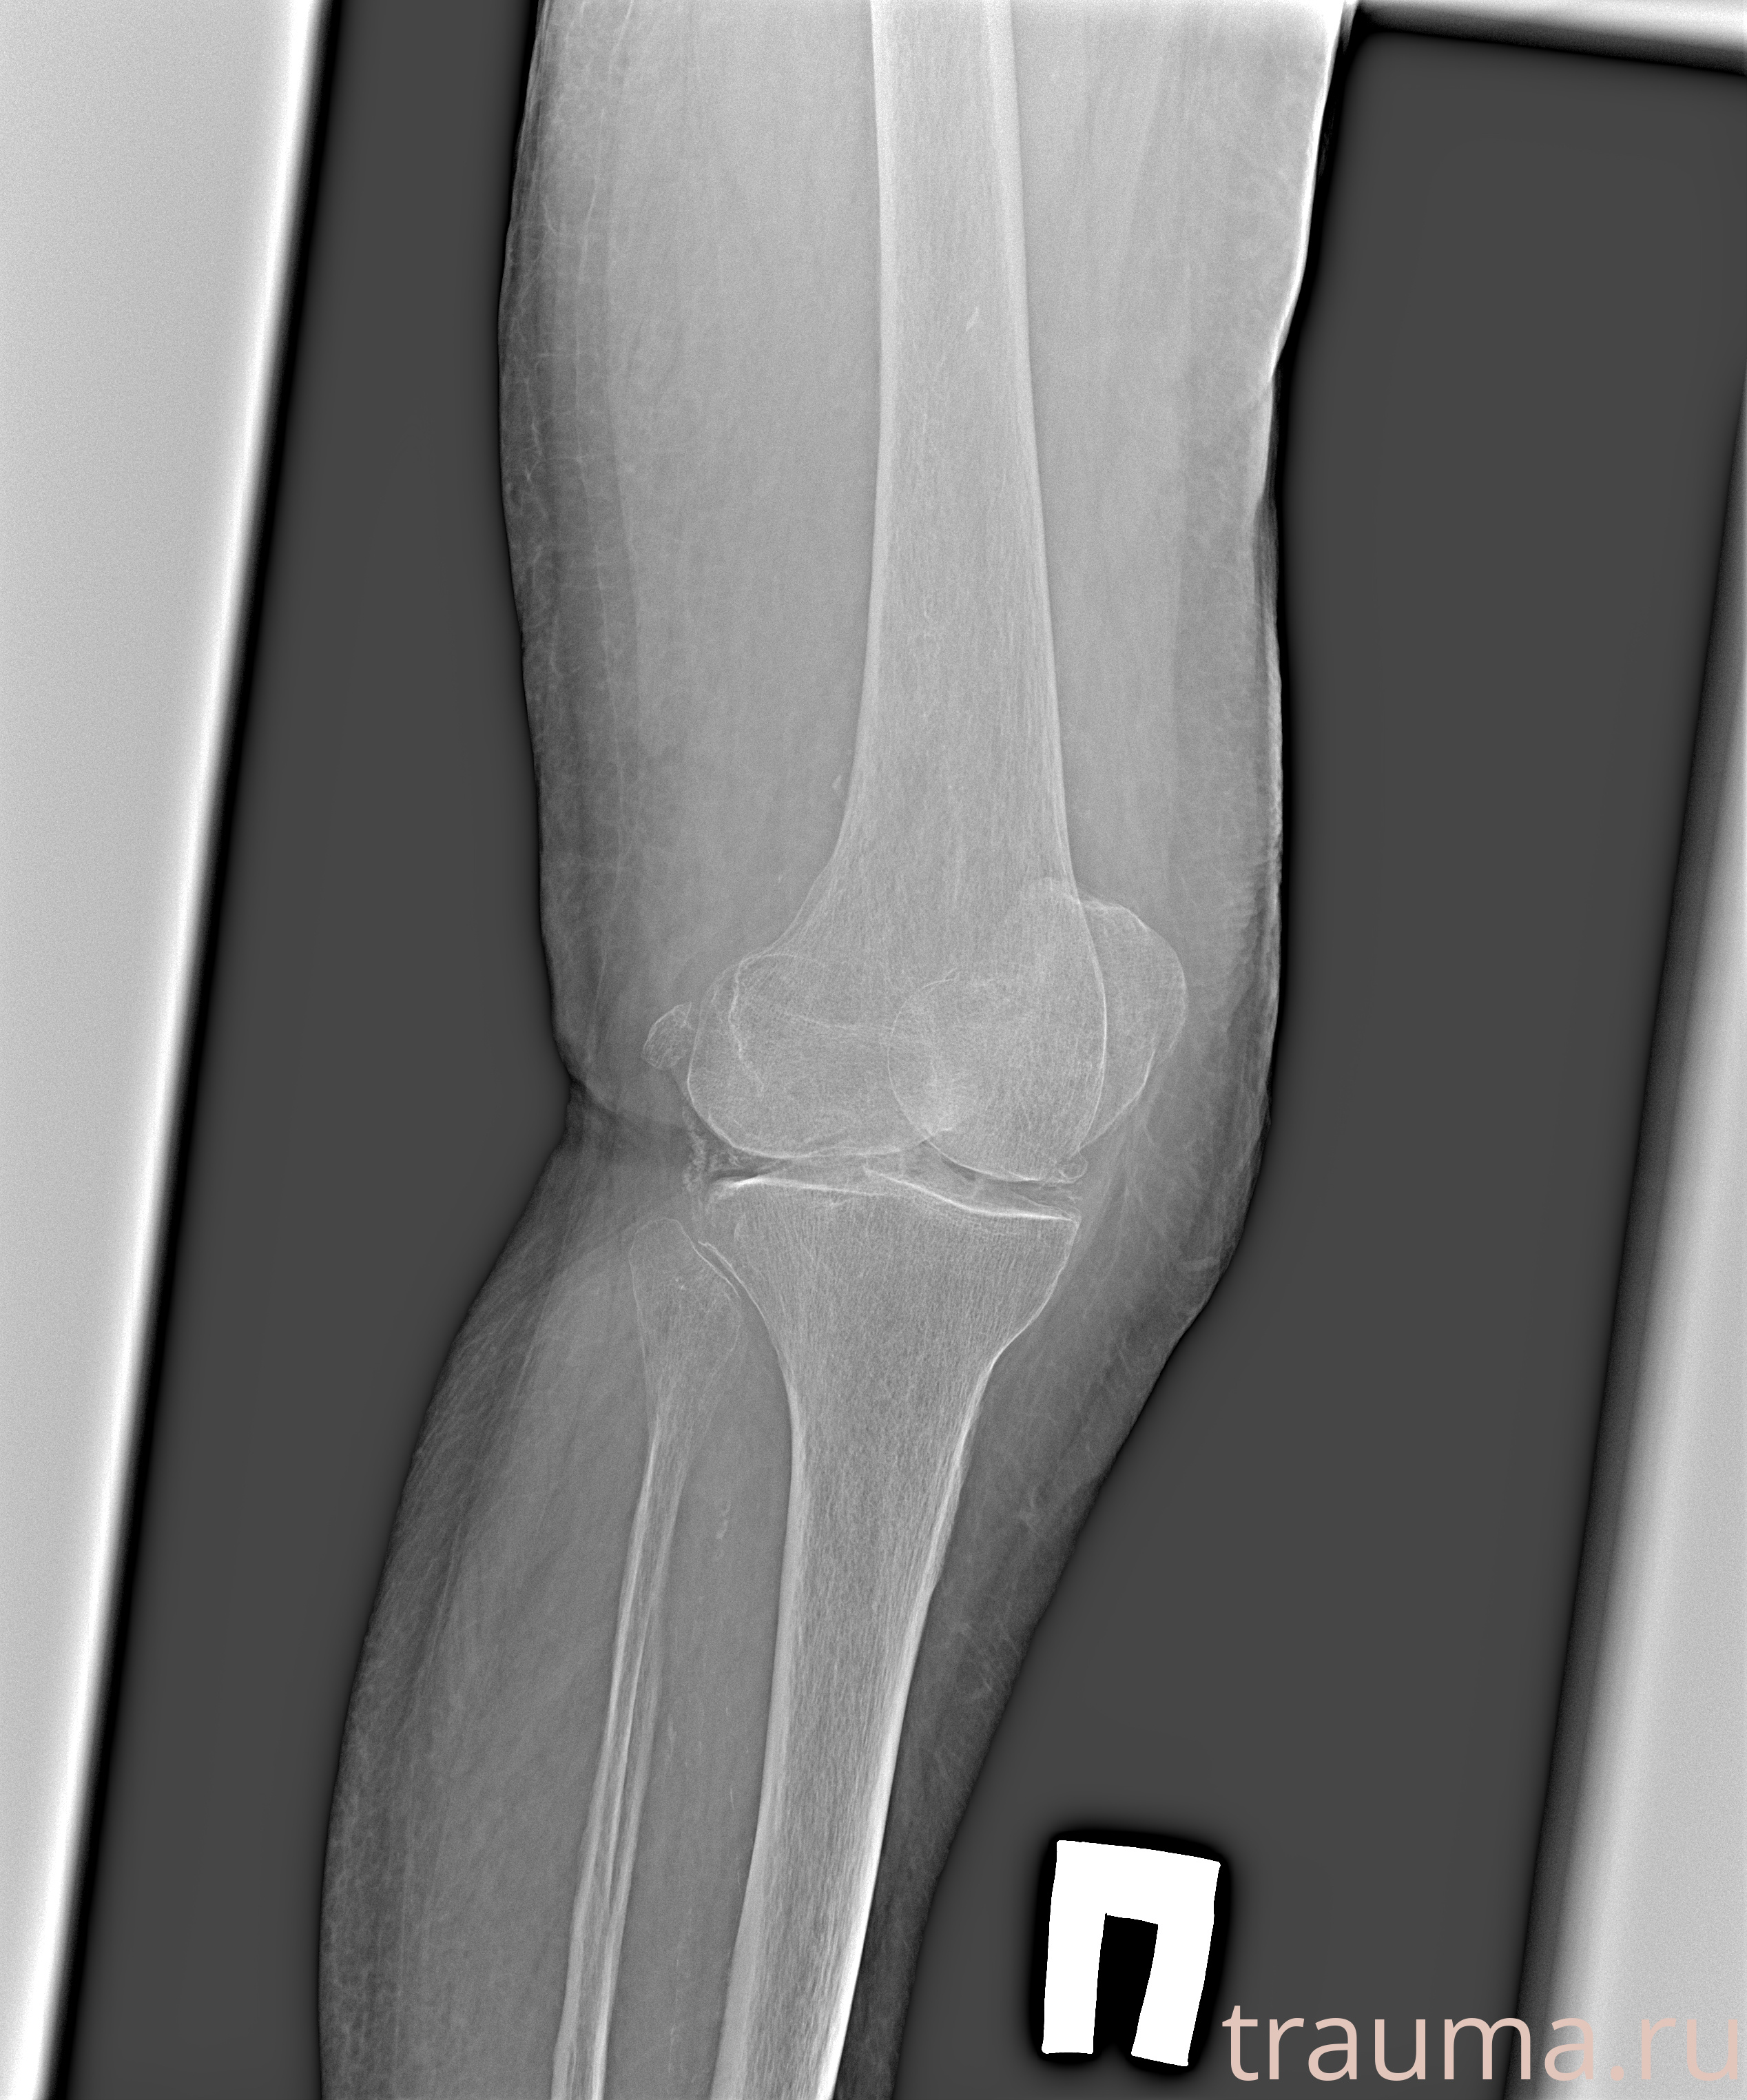

Рентгенограммы

Рентген на дому: по вашему адресу приезжает врач-рентгенолог, травматолог-ортопед с мобильным рентгеновским аппаратом, проводит диагностику травмы или заболевания, делает необходимые рентгенограммы, дает рекомендации по дальнейшему лечению. Получить качественные снимки в домашних условиях возможно благодаря уникальной методике, разработанной МосРентген Центром для института  Склифосовского